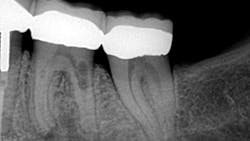

This actually has a huge bearing on dealing with resorption. External resorption versus internal resorption—when diagnosing, it makes all the difference. In my hands (and heart), I believe the only type that stands any chance whatsoever of treatment success is internal resorption. And even then, it depends on the extent of the damage.

When evaluating and discussing external resorption, I commonly tell my patients, “I cannot make your bones and gingiva stop eating the tooth. I do not have that power.” As we have all seen, external resorption can occur in various places and teeth. However, it almost always seems to be around the area of the alveolar crest, which, in my opinion, makes restoring it almost impossible. At least with internal resorption, one has a chance. You must be aggressive in cleaning the canal way beyond the typical endo and particularly in the areas of the defect. That, my friends, is where the microscope comes in very handy.

Unless it is caught on the early end, it does not matter. Once the resorptive damage has extended beyond a certain point, the prognosis drops precipitously, regardless of whether it started internally or externally. If communication of the defect occurs from internal to external or vice versa, I find that the prognosis goes from questionable to hopeless.